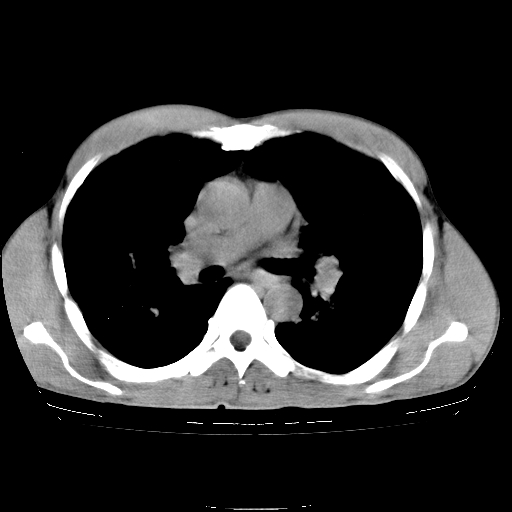

以下是引用yangyudong333在2008-4-29 5:38:00的发言:[br]比较典型的矽肺结节.支持[br]诊断依据:[br] 1.x线表现:[br] ①典型矽肺为多发直径 1~3mm 小结节,即矽结节,由胶原纤维和硅尘构成,可融合成团块,好发于上肺。[br] ②团块周围常有肺大泡。[br] ③胸内淋巴结增大、钙化。如肺门淋巴结呈蛋壳样钙化有助于与其他尘肺区别。[br] ④胸膜常广泛粘连、增厚。[br] 2.ct表现[br] ①两肺散在大小较为一致的小结节影,其密度较高,边界清楚。[br] ②小结节可融合为较大团块影,直径约 1cm ,甚至可达 10cm以上,易发生在上叶。[br] ③小结节周围常并有小叶中心气肿或弥漫性肺气肿。

以下是引用liuyue在2008-4-28 22:30:00的发言:[br]比较典型的矽肺结节.[br]请结合临床及化验除外矽肺合并肺结核之可能.